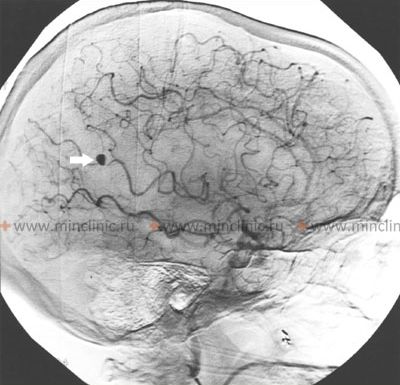

- DSA (ციფრული სუბტრაქციული ანგიოგრაფია): ითვლება ოქროს სტანდარტად მიკოზური ანევრიზმების (რაც შეიძლება იყოს მრავლობითი) საბოლოო დიაგნოსტიკისთვის, დახასიათებისთვის (ზომა, ფორმა, ლოკაცია) და იდენტიფიცირებისთვის [1, 3, 5]. ეს არის ინვაზიური პროცედურა, მაგრამ გთავაზობთ ცერებრალური სისხლძარღვების უმაღლესი რეზოლუციის ვიზუალიზაციას.

ცერებრალური არტერიების მიკოზური ანევრიზმები ვლინდება ინფექციური ენდოკარდიტის დიაგნოზის მქონე პაციენტების დაახლოებით 2-10%-ში [3, 4]. ისინი შეადგენენ ყველა დიაგნოსტირებული ინტრაკრანიალური ანევრიზმის დაახლოებით 2.5-6%-ს[1, 3]. ამ ინფექციური ანევრიზმების დაახლოებით 75% აზიანებს შუა ტვინის არტერიის (MCA) ტერიტორიის დისტალურ ტოტებს, ხოლო დანარჩენი ნაწილდება სხვა ცერებრალურ არტერიებში (წინა ტვინის, უკანა ტვინის, ვერტებრობაზილარული სისტემა) [1, 3]. მათი დამახასიათებელი დისტალური ლოკაცია მკვეთრად განსხვავდება ტიპიური ტომრისებრი ანევრიზმებისგან, რომლებიც უპირატესობას ანიჭებენ პროქსიმალურ ლოკაციებს და მთავარ ბიფურკაციებს ვილისის წრის მახლობლად [1, 3].